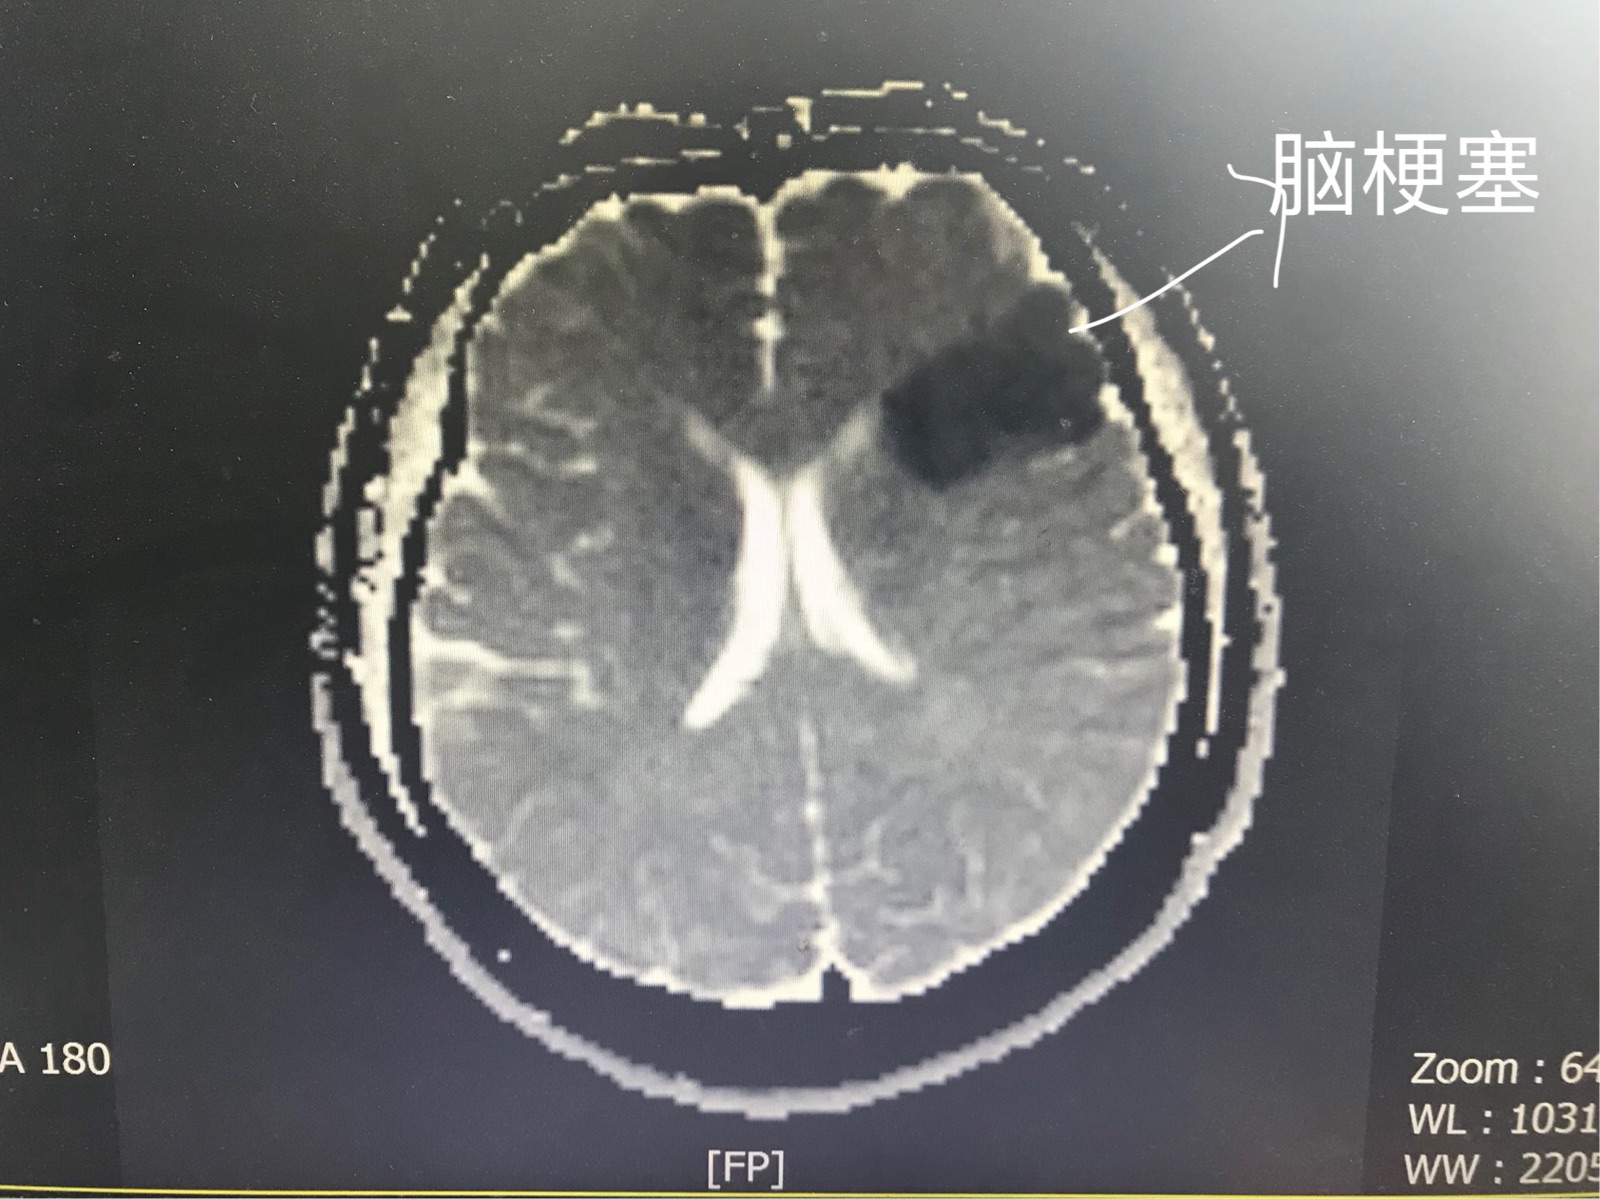

患者女,61岁,入院前3天当地医院行颈动脉彩超提示左颈动脉重度狭窄达到百分之90,让患者吃药,刚过2天颈动脉斑块脱落就脑梗塞,失语,说不出话,血沥沥的教训,有问题得早点处理,两周后行颈动脉支架植入术,患者术后3天康复出院

术前造影,脑供血较差